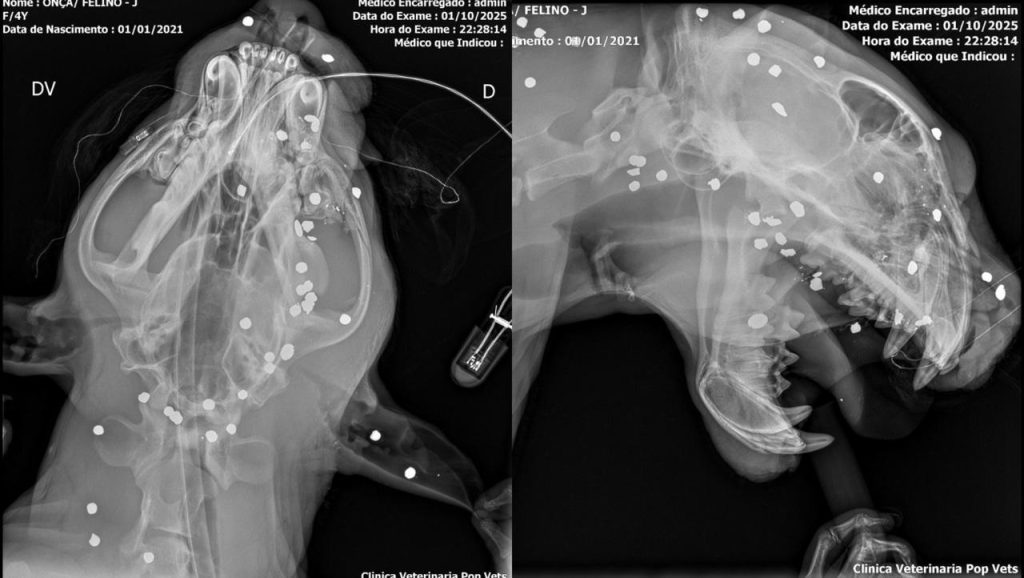

Um exame de raio-x feito na onça-pintada resgatada pelo Batalhão de Policiamento Ambiental na tarde de quarta-feira (1), nas proximidades da Praia da Ponta Negra, Zona Oeste de Manaus, revelou a posição dos mais de 30 projéteis de chumbinho que foram disparados contra o animal.

A maioria dos disparos atingiu a cabeça e o pescoço da onça, que já apresentava sangramentos e sinais de exaustão no momento do resgate. A onça perdeu dentes e apresentava edemas nos olhos e orelhas.